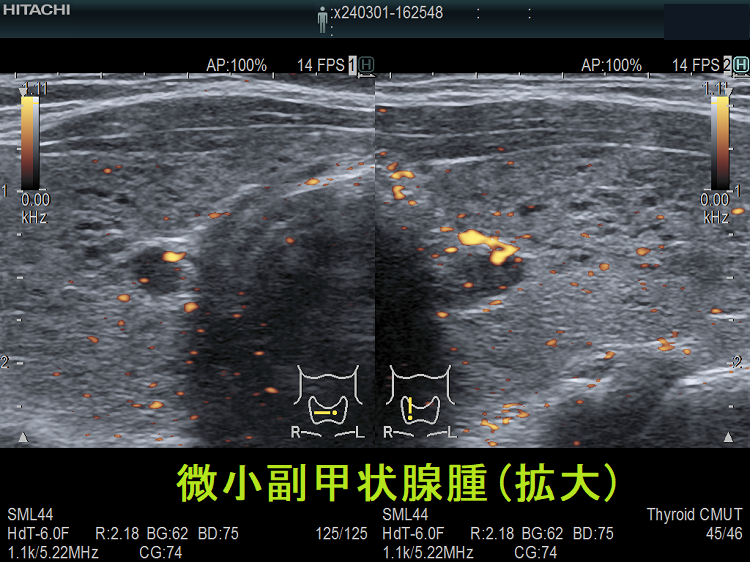

(➸)原因となる副甲状腺腺腫、副甲状腺癌、副甲状腺過形成をデジタルハイビジョン超音波診断装置で診断。エコーでは、甲状腺とのインピーダンスの違いにより、甲状腺-副甲状腺境界部に線状高エコーが生じます(右図の↓)。内部は中心血流を認め、リンパ節でないのが分かります。

微小副甲状腺腫;血清カルシウムは正常範囲内の上限だが、脱水などの影響で上限を超える場合もある。骨密度は正常で、腎結石(腎臓結石)もない。

血清カルシウム・リン値正常、副甲状腺ホルモン(PTH)濃度も正常の副甲状腺腺腫が存在します。甲状腺超音波(エコー)検査で偶然見つかるケースがほとんどで、さほど大きくないためCT/MRIでは見えない場合が多いです。もちろん、副甲状腺機能亢進していないため治療適応にはなりません。副甲状腺ホルモン(PTH)合成能が低い副甲状腺腺腫ですが、年次フォローするとサイズが増大して、高カルシウム血症・副甲状腺機能亢進症に進展することもあります。[World J Surg. 2017 Jan;41(1):122-128.][Aust N Z J Med. 1998 Apr;28(2):173-8.]

甲状腺内副甲状腺腫は、超音波(エコー)検査で甲状腺腫瘍と形態的に鑑別できない場合があります(実際は下の写真のように診断できていますが・・)。特徴的な超音波(エコー)所見は、腹側の高エコーで感度86%、特異度100%です[Surgery. 2012 Dec;152(6):1193-200.]。さらに、99m-Tc MIBIシンチグラフィーで取り込み(集積)があれば甲状腺内副甲状腺腫と診断できます。